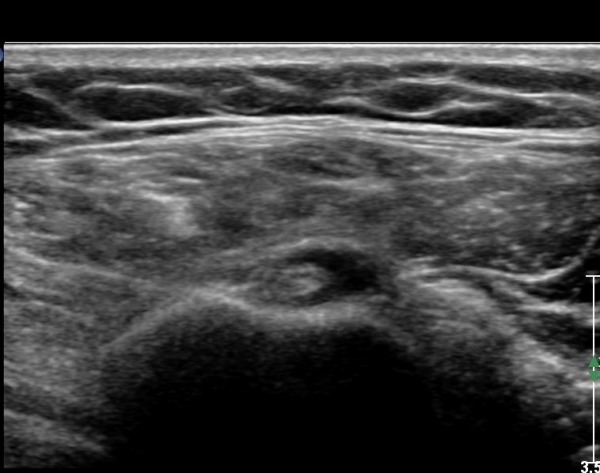

ÃÊÀ½ÆÄ ¼Ò°ß: ¿À±¸µ¹±â¿Í °ßºÀÀ» ¿¬°áÇÏ´Â ¿À±¸µ¹±â°ßº»Àδ밡 Á¤»óÀûÀÎ ¸ð½ÀÀ¸·Î °üÂûµÈ´Ù(»çÁø 1).

ŽÃËÀÚ¸¦ Á¶±Ý ¸»´ÜÀ¸·Î À̵¿ÇÏ´Ï ¿À±¸µ¹±â°ßºÀÀÎ´ë °ßºÀ ºÎÂøºÎ °ñ±ØÀÌ °üÂûµÇ°í Àδë

½ÉÃþºÎ¿¡ ¼ö¾×Àú·ù°¡ ÀÖ¾î ¸¸¼ºÀûÀÎ Ãæµ¹À» ÃßÁ¤ÇÒ ¼ö ÀÖ´Ù(»çÁø 2).